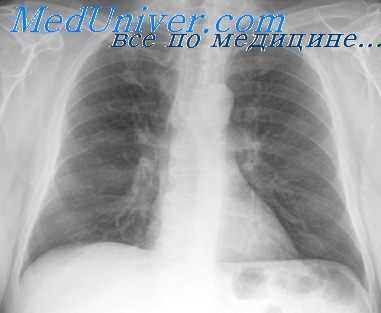

Рентгенологическая картина после торакопластики. На обзорных рентгенограммах и томограммах после экстраплевральной Т. определяется уменьшение объема оперированной половины грудной клетки и спадание соответствующего легкого. Степень уменьшения объема грудной клетки и легкого на оперированной стороне зависит от вида и объема Т. Рентгенологические изменения в легких наблюдаются при возникновении пневмонии, иногда осложняющей послеоперационное течение. В первые дни после операции могут возникать массивные ателектазы, в свою очередь осложняющиеся пневмониями. После обширной Т. может наблюдаться флотирование (маятникообразное смещение, синхронное с дыханием) средостения в области дефекта грудной стенки, исчезающее по мере регенерации костной ткани из оставшейся надкостницы ребер.

В отдаленные сроки после операции спавшееся легкое частично расправляется и вентиляция его улучшается за счет увеличения амплитуды дыхательных движений диафрагмы и ребер на стороне оперативного вмешательства, что отчетливо определяется на рентгенокимограмме (см. Рентгенокимография). В ряде случаев расправления легкого в отдаленные сроки не происходит вследствие развития в нем после операции пневмосклероза (см.), а иногда в последующем — бронхоэктазов (см.).

Определяемые после Т. тени регенерировавших ребер, особенно на фоне массивных плевральных шварт, затрудняют распознавание остаточных каверн и щелевидных остаточных полостей эмпием в случае неэффективной операции. Томография (см.) облегчает диагностику каверн в спавшемся легком, а фистулография (см.) и бронхография (см.) — выявление остаточных полостей.